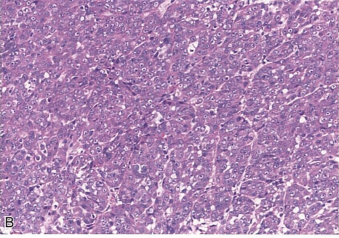

患者女,45岁。1年前发现左大腿后侧包块,质韧,活动差。1年来,包块逐渐增大,并出现疼痛。查体:左大腿后侧可见3cm×3cm包块,质韧,边界清,活动差。超声:左侧腘窝上方见一混合回声团块,大小:23mm×23mm,边界欠清。镜下观察包块形态如图所示。